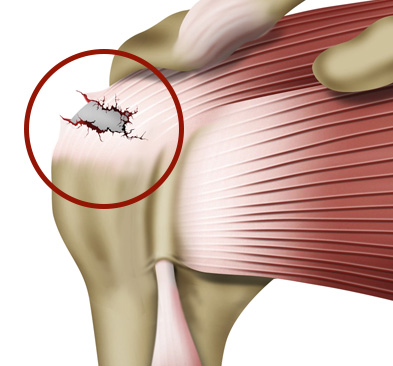

이런 회전근개가 하나 또는 그 이상 파열되는 것을 회전근개 파열이라고 합니다.

회전근개파열은 파열정도에 따라서 치료법이 달라집니다.

회전근개 파열의 원인은 여러 가지가 있으나

반복적인 움직임이나 과도한 사용으로 인해 근육에 스트레스가 가해지거나, 염증이나 건염 등의 원인으로 힘줄이 약해지면 파열의 위험이 생깁니다.